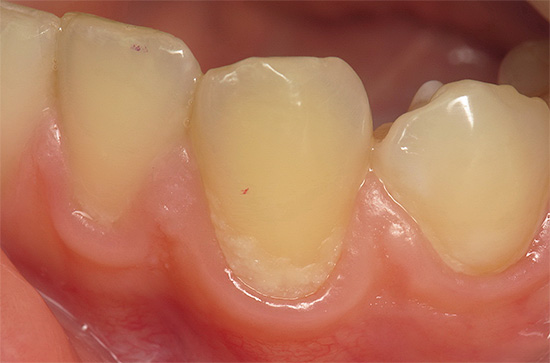

E in questa foto - carie profonde, che già minaccia di svilupparsi in pulpite:

Con la carie profonda, come suggerisce il nome, gli strati profondi di dentina sono interessati fino alle aree vicino alla polpa. Se la polpa stessa è interessata, la pulite inizia con dolore acuto e il rischio di infiammazione parodontale.